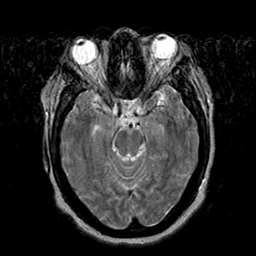

Cerebral hemorrhage, MR Study mr-t2 -- Slice #9

[Home][Help][Clinical] Slice 9